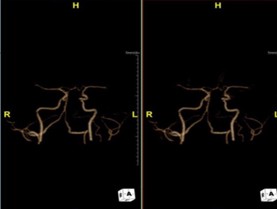

Những năm vừa qua được sự quan tâm của thủ trưởng các cấp cùng với sự đầu tư của Đảng ủy, Ban giám đốc Bệnh viện trong chẩn đoán và điều trị, bệnh viện đã trang bị nhiều máy móc hiện đại, trong đó đặc biệt có máy CT Scanner 16 Slice SIEMENS của Cộng Hòa Liên Bang Đức, cùng với sự chuyển giao kỹ thuật, công nghệ mới, các bác sỹ và kỹ thuật viên đã làm chủ hoàn toàn các kỹ thuật phức tạp mà chỉ có tuyến tỉnh và trung ương mới đáp ứng được như: Chụp CTscanner có thuốc cản quang gan ba thì, ổ bụng, lồng ngực, sọ não, hệ mạch máu bụng, chậu, chi…Trong thu dung cấp cứu, máy CT Scanner càng phát huy thế mạnh trong chẩn đoán chấn thương sọ não, chấn thương bụng kín…